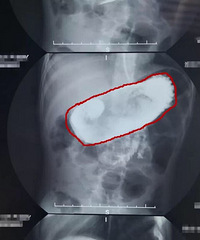

渝北财富大道3号财富汇一楼的面馆,打包了个小面,一翻就发现了个大蟑螂,当时真是想吐,幸好还没开始吃,去店头找人,煮面的像个黑社会,嚣张得很,问